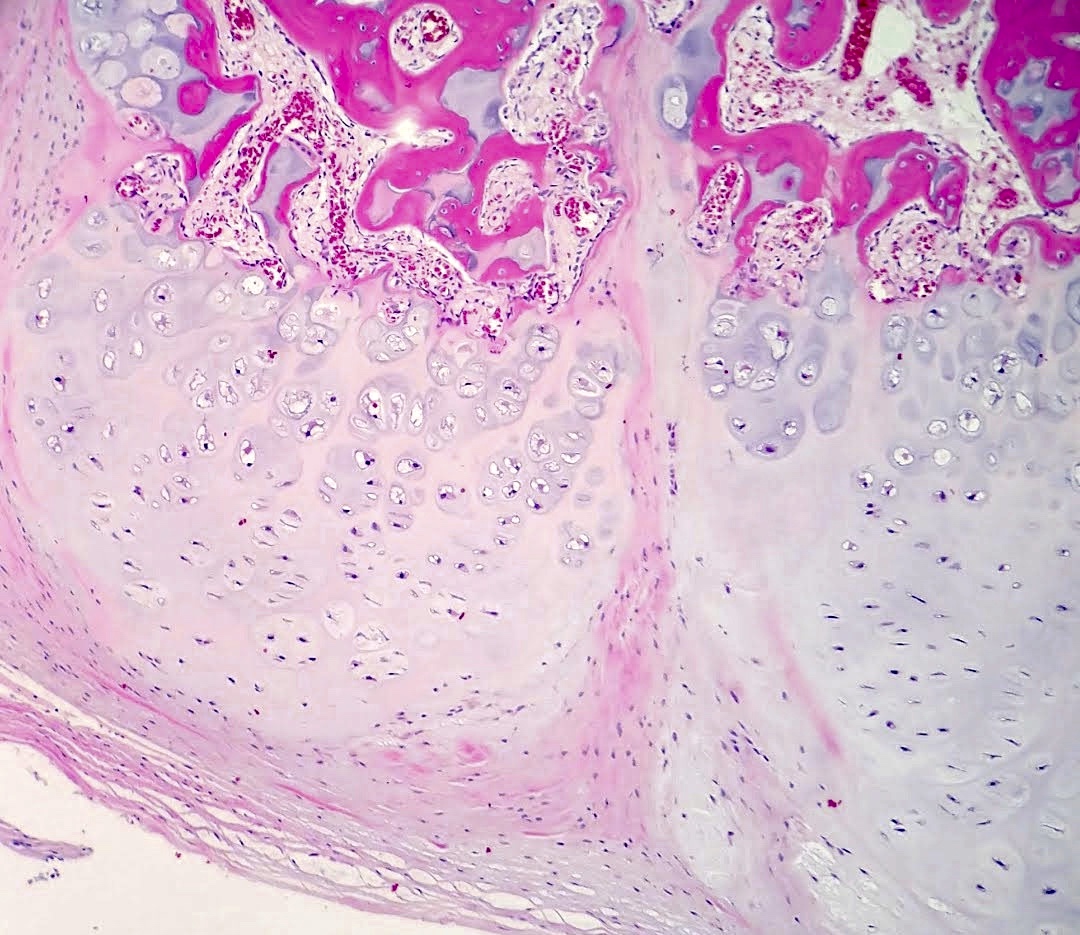

Microscopic (histologic) description

- Cap composed of mature hyaline cartilage with overlying fibrous perichondrium

- In young patients, transition between bone and cartilage cap resembles growth plate, showing endochondral ossification into mature bone; cartilage cap diminishes and may essentially be absent in older adults

- Marrow elements may be present within bony stalk; marrow space / cancellous bone contiguous with that of the native bone

Microscopic (histologic) images